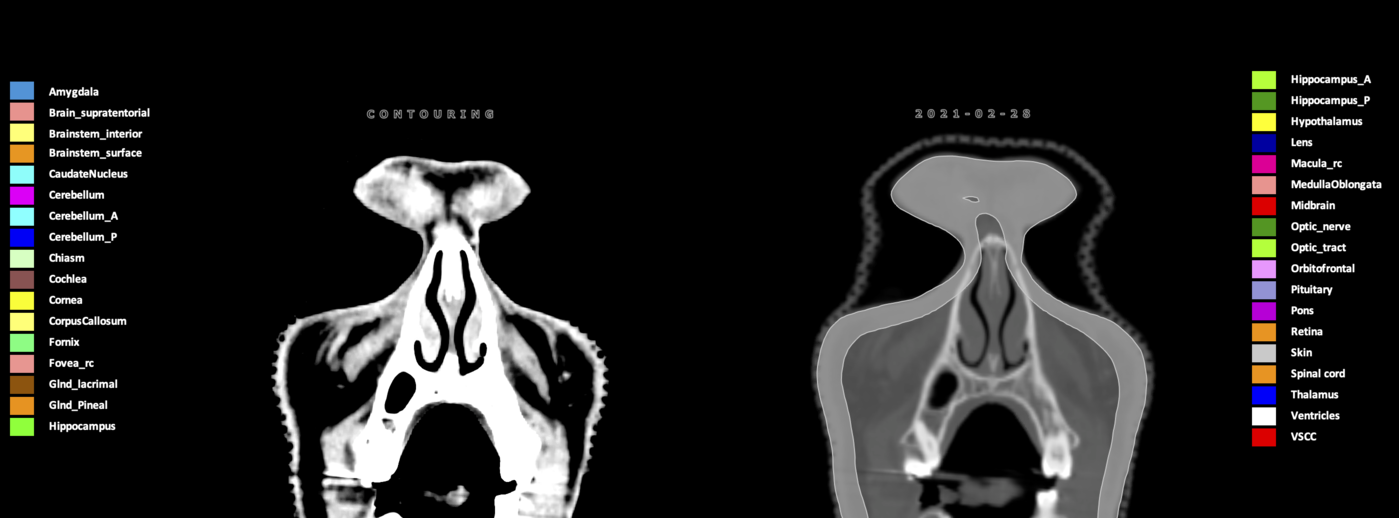

Eekers et al. have published an international neurological atlas for contouring of organs at risk in consensus with the European Particle Therapy Network (EPTN) in 2018 and an update in 2021. The purpose of this consensus atlas is to decrease inter- and intra-observer variability in delineating OARs relevant for neuro-oncology.

Included are all OARs known to be relevant for radiation-induced toxicity in neuro-oncology: brain, brainstem (midbrain, pons, medulla oblongata), chiasm, cerebellum (anterior & posterior), cochlea, cornea, hippocampus (anterior & posterior), hypothalamus, lens, lacrimal gland, optic nerve, pituitary, skin, and vestibular & semicircular canals. To further facilitate research on cognition, vision and radiological changes after irradiation of the brain, potential clinically-relevant OARs are included: amygdala, caudate nucleus, cerebellum (anterior & posterior), corpus callosum, fornix, macula, optic tract, orbitofrontal cortex, periventricular space (PVS), pineal gland, and thalamus.

Three-dimensional delineation of the 25 consensus OARs for neuro-oncology are shown on CT (WW/WL 120/40, 3000/600), 3T MR images, (T1Gd, T2FLAIR 1mm) and 7T MR (MP2RAGE 0.7 mm). All are presented in transversal, sagittal and coronal view.